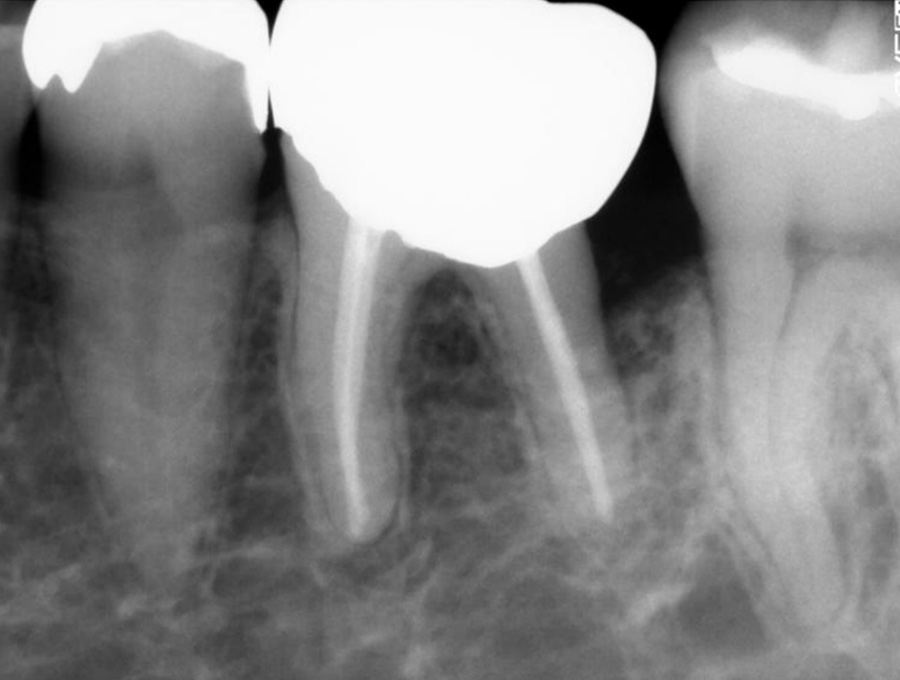

04

抜歯になった際の

インプラントインプラントも対応

歯周病により破壊された、歯茎や骨を人工骨や成長因子などを用いて再生させる治療方法です。将来的に抜歯となるリスクの高い歯などを歯周組織を再生させ、歯を長持ちさせることを目的とします。歯周病でダメになった歯をどうしても残したい方、歯ぐきや歯槽骨を元に戻して歯の寿命をしっかり伸ばしたい方に適応される治療方法です。